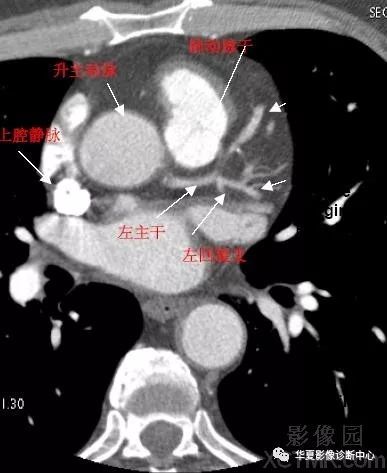

影像解剖|心脏冠状动脉ct解剖中文详细标注(图文)